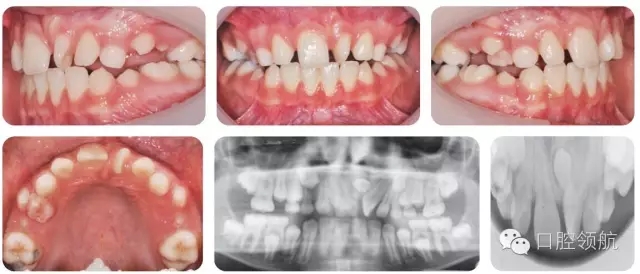

10歲的男性患者,由全科牙醫(yī)轉(zhuǎn)診。該患者健康情況良好,主訴是上前牙不美觀(圖2.16)。

圖2.16

● 混合牙列,III類切牙關(guān)系,前牙覆減小但未出現(xiàn)開牙合。

● 雙側(cè)磨牙1/2牙尖II類關(guān)系。

● 上中線左偏。

● UL1近中腭側(cè)旋轉(zhuǎn)。

上頜中線處存在未萌出的多生牙。

上頜中線處多生牙。形態(tài)為錐形,倒置。可能是正中多生牙。